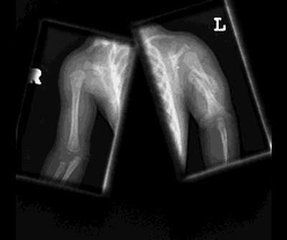

成骨不全骨折的原因

1、轻微的暴力

2、非创伤性外力

3、不明原因(同一部位多次骨折,渐进性的骨骼畸形!)

如何判断骨折?

疼痛、肿胀、活动受限

骨折特有体征

1、畸形:骨折端移位使患肢外形发生改变,主要表现为缩短、成角、延长。